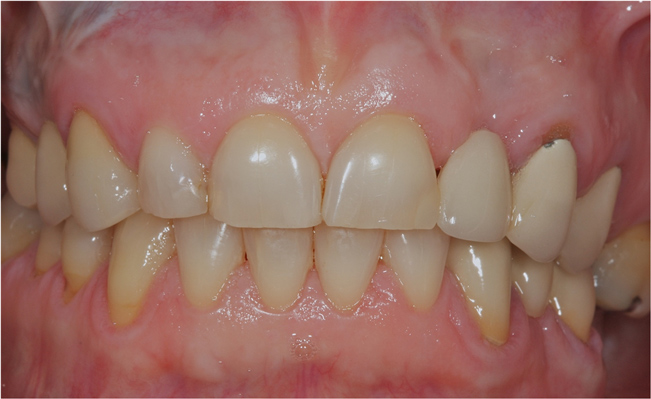

A 28-year-old woman in excellent health presented chiefly to enhance her dental esthetics and eliminate the central diastema (Figure 1 and Figure 2). While this seemed to be a potential veneer case, a comprehensive diagnosis—including the evaluation of mounted models on a fully adjustable articulator—confirmed the clinical findings of vertical dimension collapse and a lack of posterior occlusion on the left side. It was not possible to treat this occlusal factor with only veneer therapy or by limiting treatment to the anterior dentition. The treatment plan was for maxillary full-coverage crown restorations with lithium disilicate to maximize esthetics, strength, and wear of the opposing teeth.6 The periodontium was healthy and there was adequate gingival symmetry, so there was no need for periodontal surgical intervention.

Figure 2 The intraoral photograph demonstrates both the esthetic and functional diagnoses, including findings of vertical dimension collapse and a lack of posterior occlusion on the left side.

Figure 2